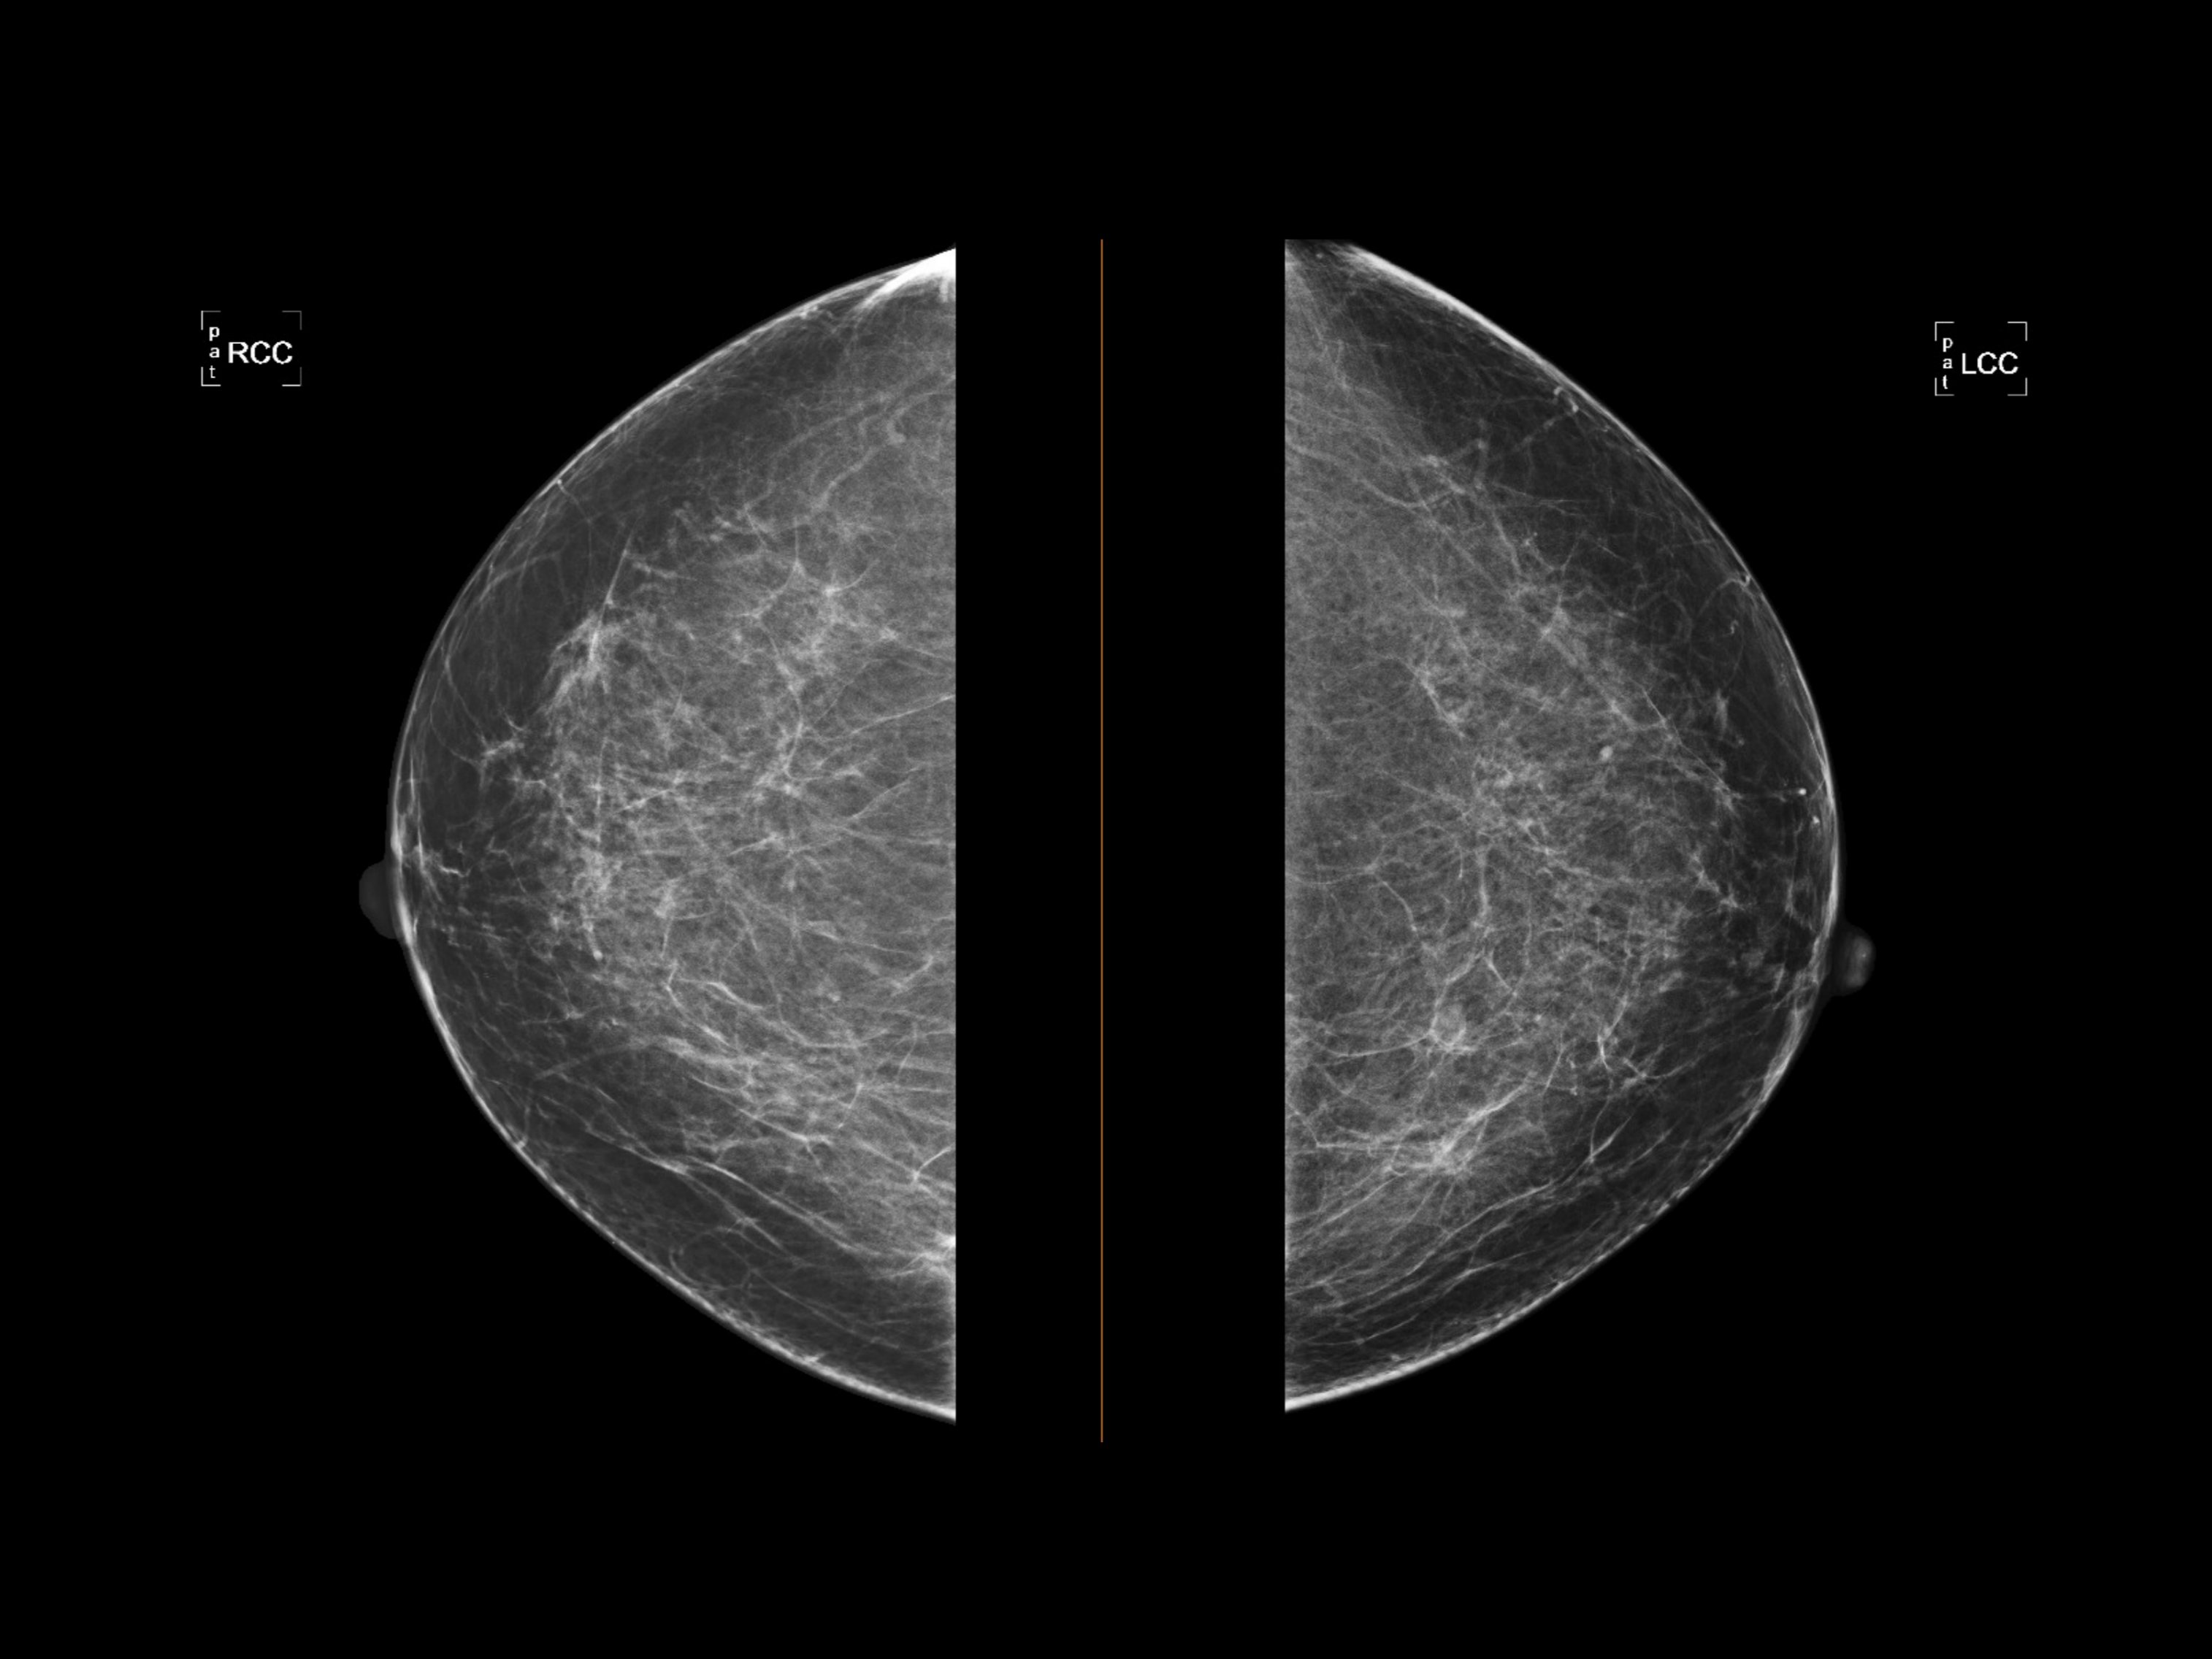

For imaging professionals, understanding the nuances of dense breast tissue and the evolving technology used to assess it is essential. Dense tissue, composed of more glandular and fibrous connective tissue than fatty tissue, poses two significant challenges. First, it is an independent risk factor for developing breast cancer. Second, it creates a masking effect on traditional mammograms. Since both dense tissue and tumors appear white on X-rays, finding a lesion can be akin to looking for a snowball in a blizzard.

Digital mammography remains the gold standard for screening, but its limitations in dense breasts are well-documented. Sensitivity can drop significantly when screening women with heterogeneously dense (BI-RADS C) or extremely dense (BI-RADS D) tissue.

While 2D mammography is efficient and effective for fatty breasts, the superposition of tissues in a 2D image often obscures small masses. This limitation has driven the rapid adoption of supplemental screening methods and advanced imaging modalities designed specifically to look through the density.